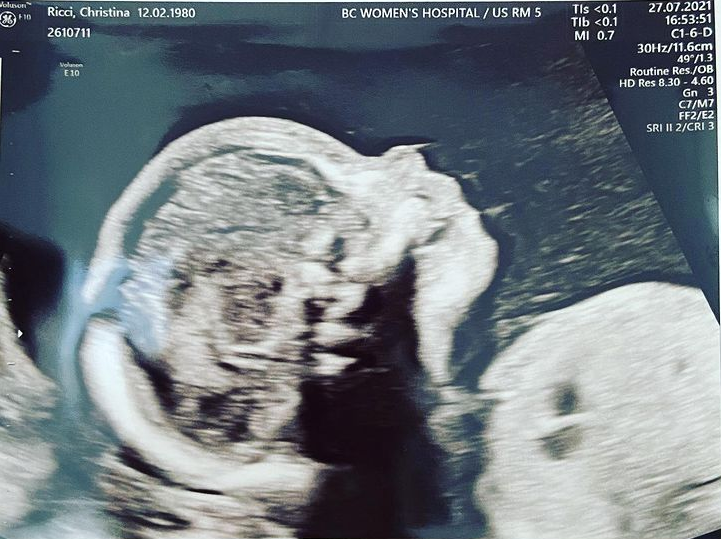

41-годишната звезда от „Семейство Адамс“, актрисата Кристина Ричи е бременна с второто си дете, съобщава People.

Новината съобщи сама тя и пусна снимка от видеозон в профила си в Instagram като под нея написа: "Животът продължава по-добре“.

Снимка: Instagram